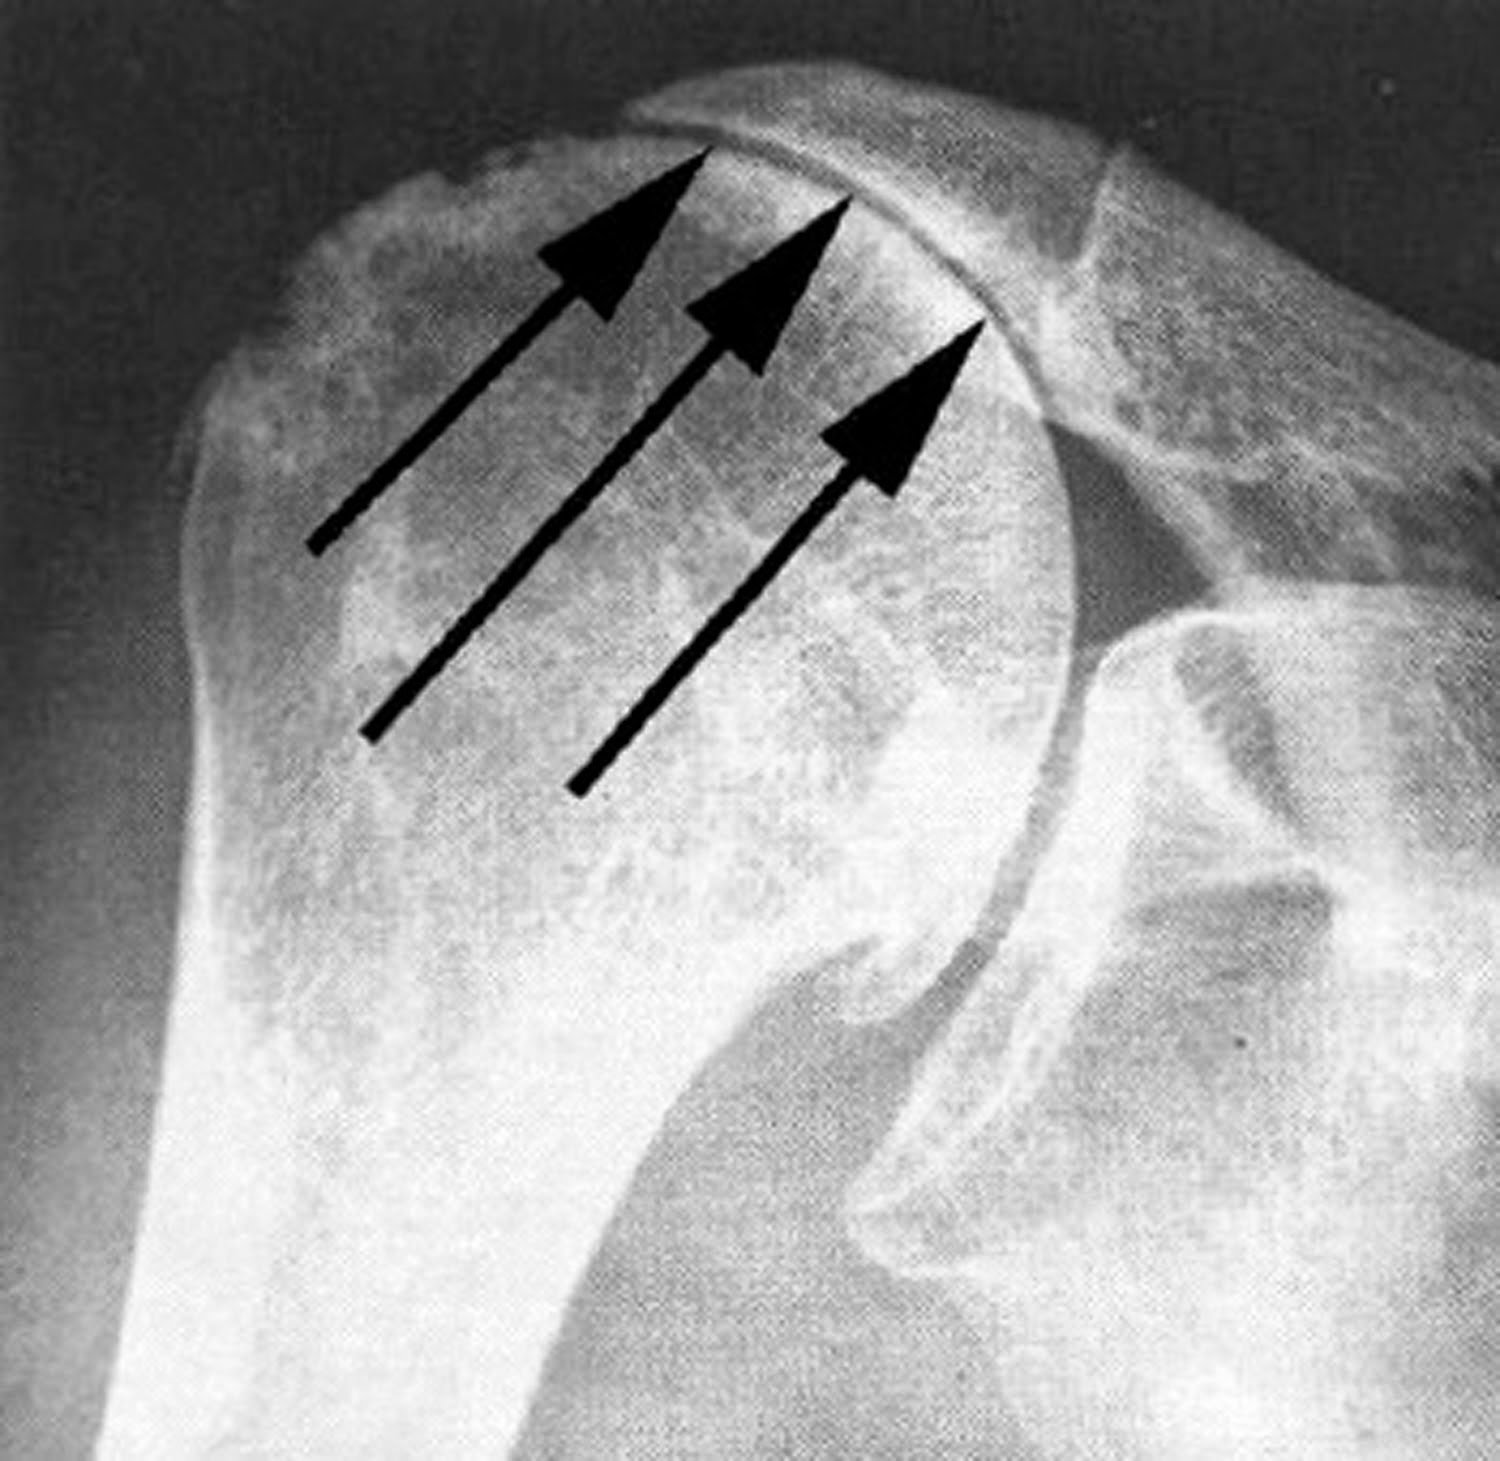

UW Shoulder and Elbow Academy Do cuff tears increase in size with time Shoulder Pain Arthritis Or Rotator Cuff The four rotator cuff tendons in your shoulder wrap around the ball portion of the shoulder joint, holding it in The rotator cuff is a group of muscles and tendons that keep the upper arm bone held in the shoulder blade socket. Rotator cuff tear arthropathy is a type of shoulder arthritis that can develop after a massive and prolonged. Shoulder Pain Arthritis Or Rotator Cuff.